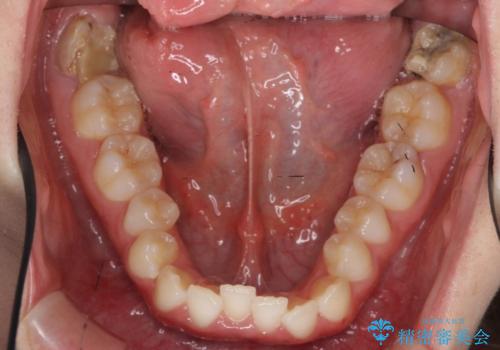

再矯正 他院の治療後の修正 出っ歯をしっかり下げました

- 出っ歯を主訴に来院。

以前他院で歯を抜かずに治療を受けたが思ったような仕上がりにならなかったとのことでした。

矯正用ミニスクリューを用いて、抜歯した隙間以上に前歯を下げています。

はじめは抜歯の本数を少なく(2本)する治療方針でした。治療途中で追加で抜歯を行い口元をさらに下げる選択をしました。

そのため、治療期間は少し長くなっています。

口元が大きく下がり、閉じやすくなりました。

患者様には大変満足していただきました。

非抜歯で無理に矯正治療をすると口も閉じにくくなり、仕上がりもキレイにならないことがあります。